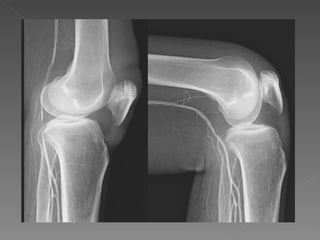

Anatomía de la rodilla

Articulación bicondilea: - Femoro-patelar o femoro-rotuliana - Femoro-tibial medial - Femoro-tibial lateral Elementos óseos: - Extremo distal de fémur - Extremo proximal de la tibia - Rotula Morfología de la rodilla